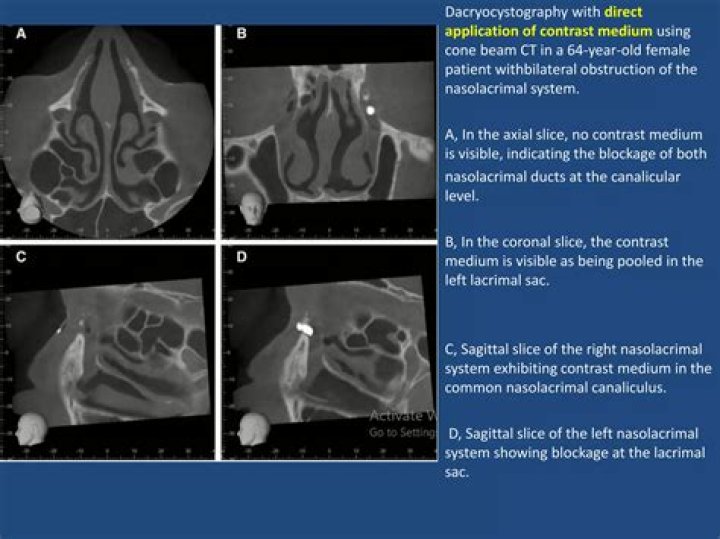

Dacryocystography (DCG) is a fluoroscopic contrast examination of the nasolacrimal apparatus. The nasolacrimal duct is cannulated enabling iodinated contrast to be instilled into the nasolacrimal system.

A dacryocystogram is a special x-ray procedure that is done to visualize the lacrimal duct of the eye following the injection of contrast media (x-ray dye) into the duct.

Dacryocystography allows the identification of the obstruction site and, in some cases, the cause of the obstruction of tear flow, which is fundamental to define the type of clinical or surgical conduct.